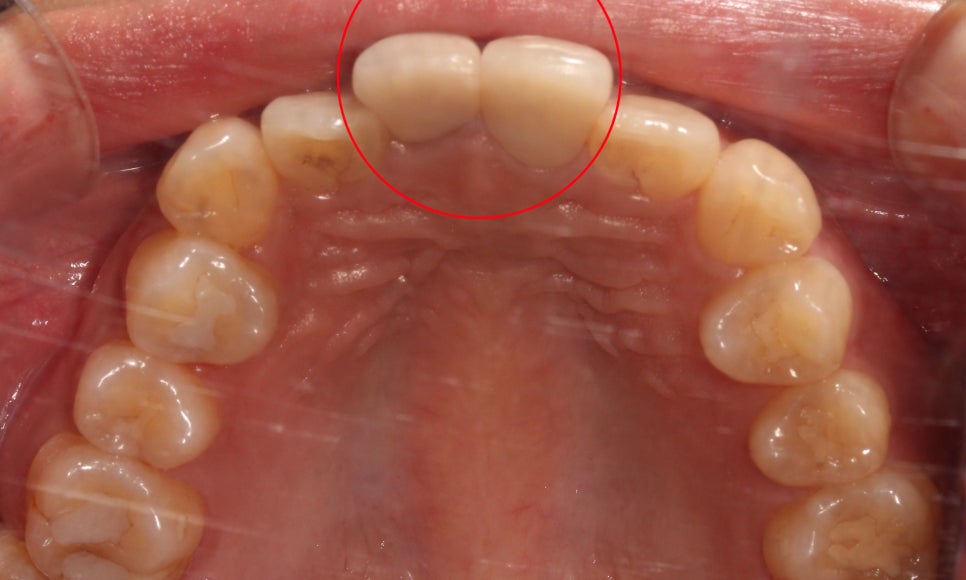

상악의 절단연을 보시면

중절치가 뻐드러지듯

돌출되어 있는 모습인데요,

측절치의 경우 중절치 옆으로

삐뚤게 맹출되어 있어

전치부의 심미성을 해치는 모습입니다.